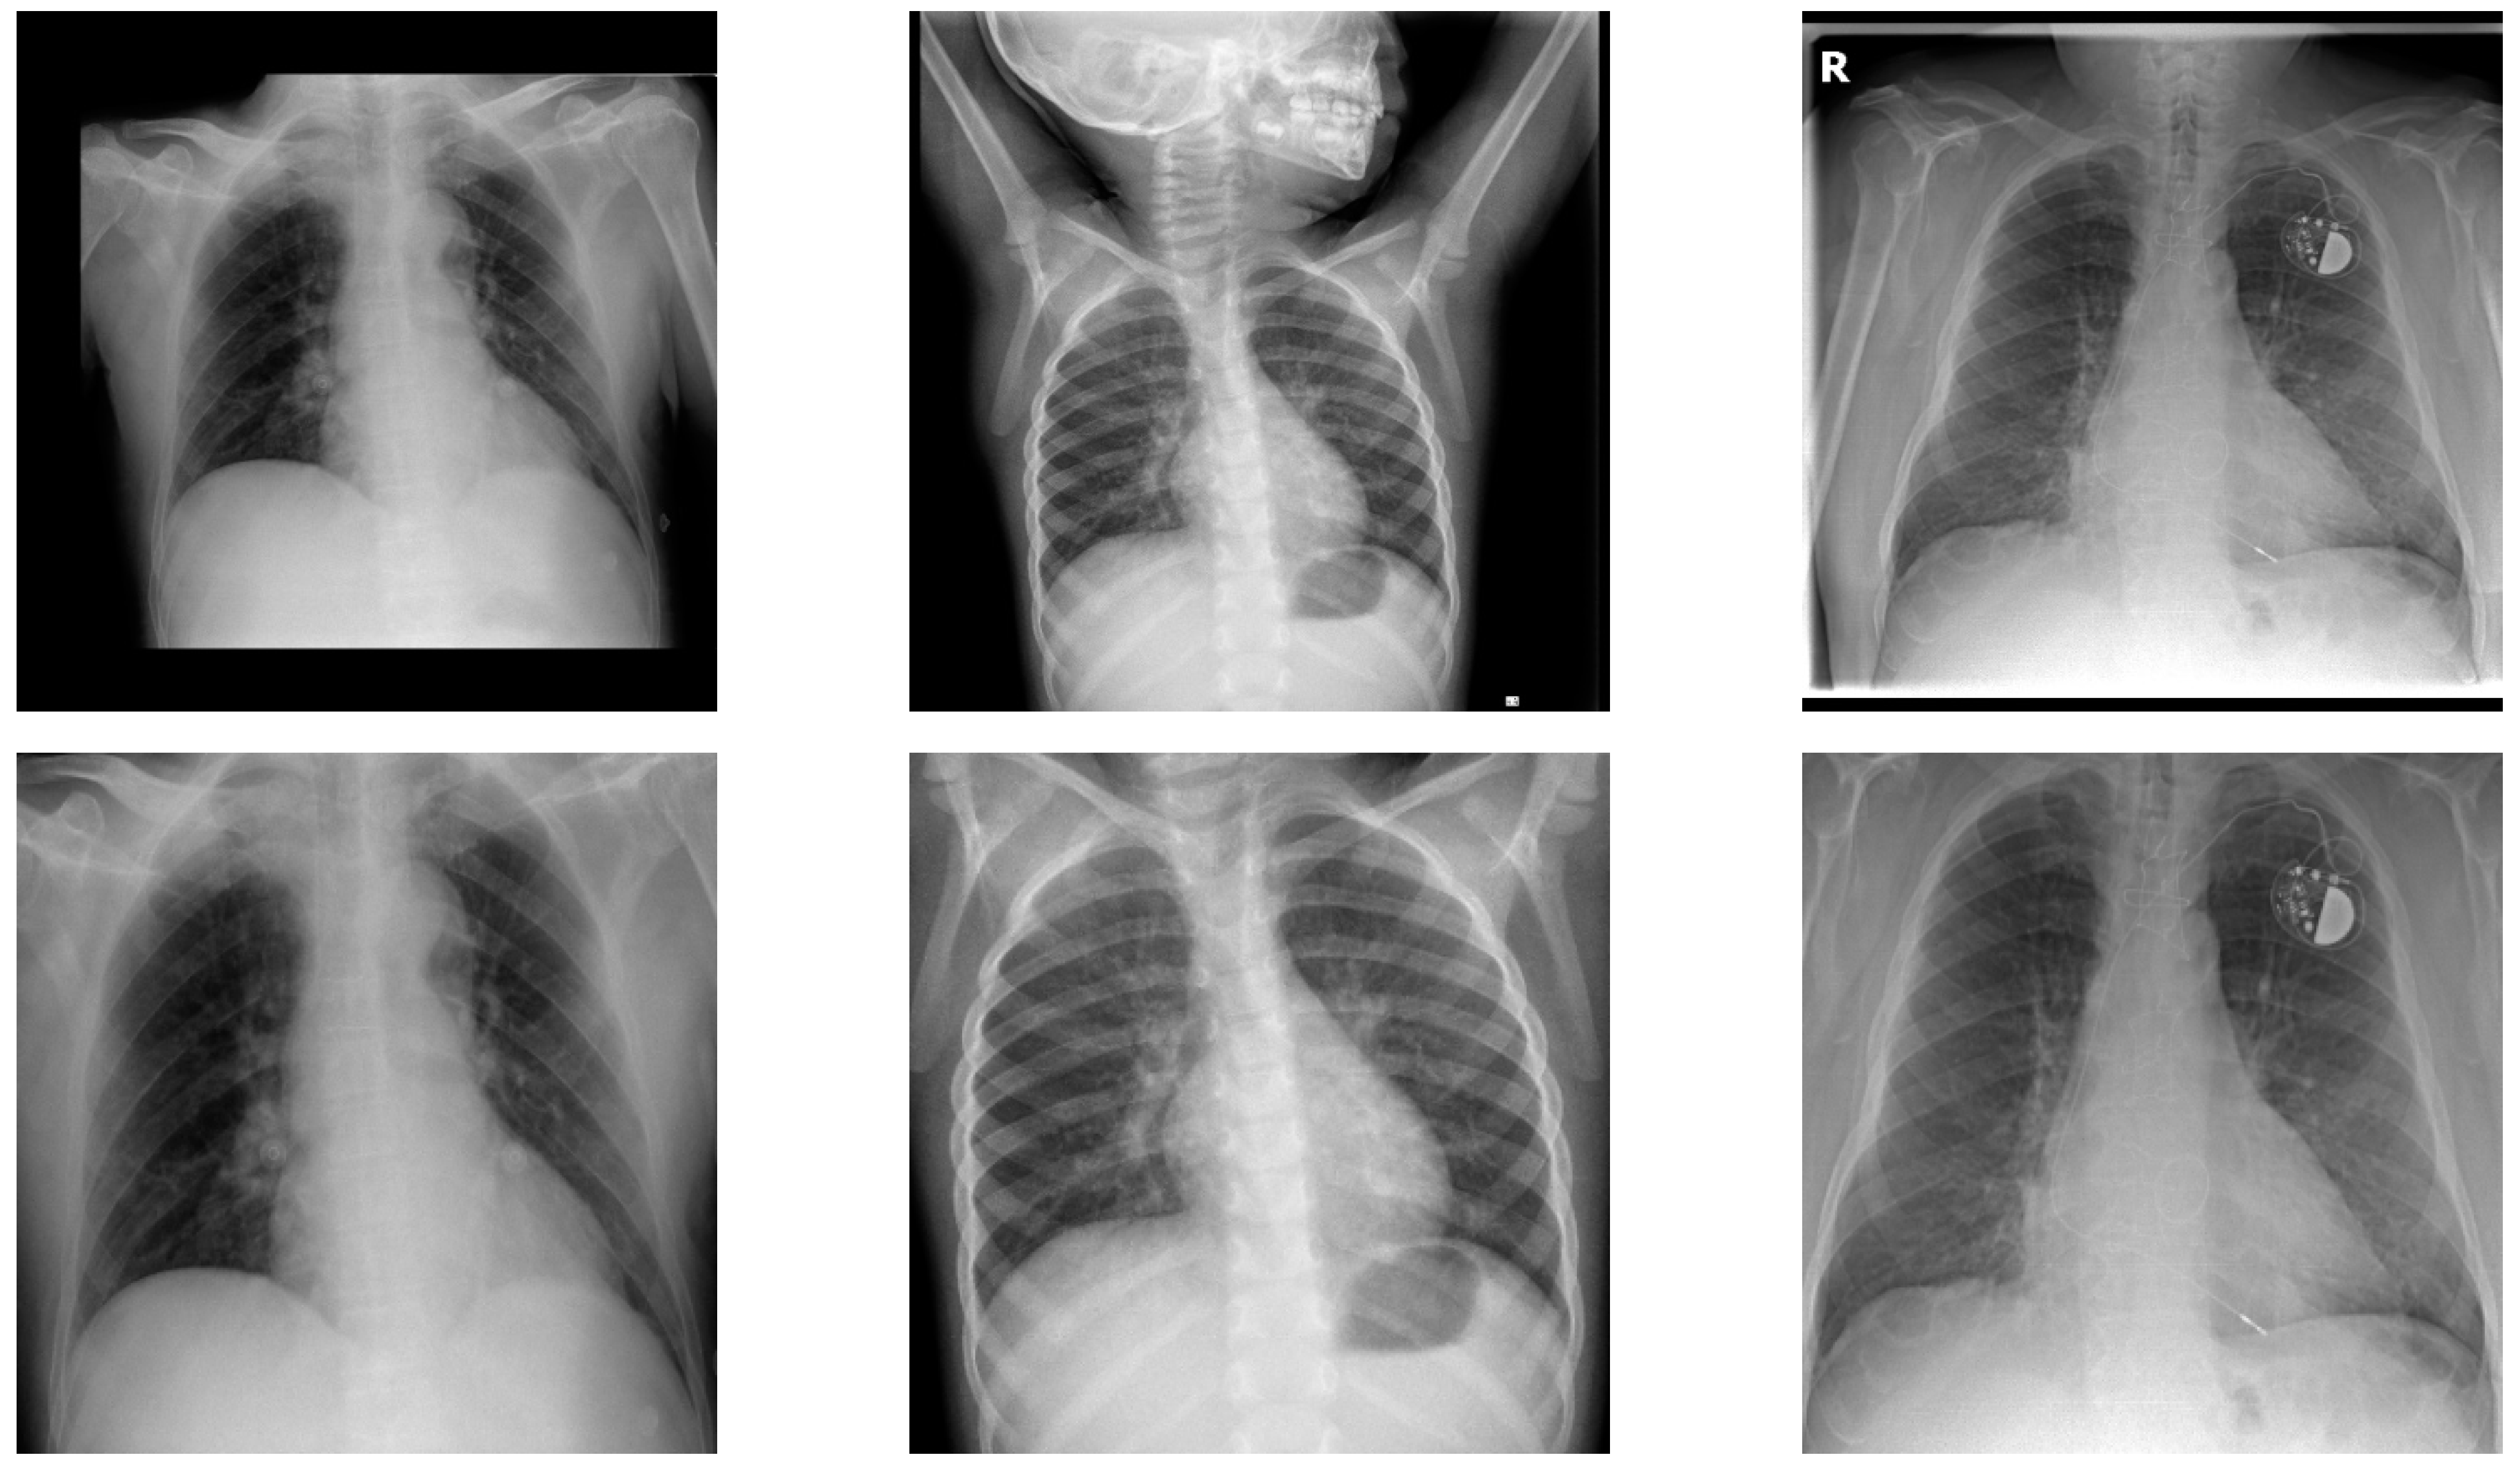

3.2.1. Lung Localization

3.2.2. Lung Segmentation